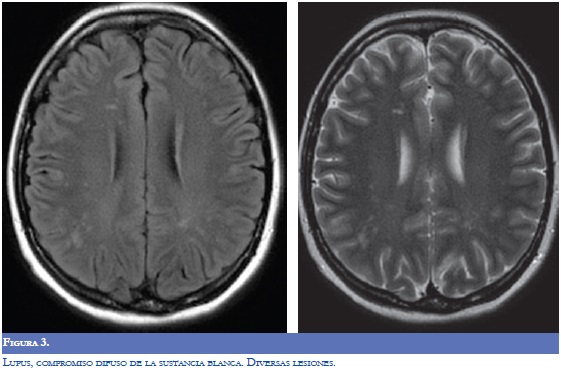

La RM (Figuras 1-4) permite valorar mejor la sustancia blanca cerebral y se pueden ver lesiones pequeñas de causas isquémicas que se presentan en el LES/SAF hasta en 30 a 70% y se asemejan a las placas desmielinizantes de la EM (2). El concepto de realce con gadolinio que sugiere inflamación no es específico para la EM, los complejos inmunes inducen la alteración de la barrera hematoencefálica, de modo que la RM como método diagnóstico no permite definir la causa. La distribución de las lesiones pueden orientar al diagnóstico y las lesiones subcorticales prevalecen en el LES/SAF y las periventriculares próximas al cuerpo calloso como lesiones ovoides (dedos de Dawson) y los hoyos negros son característicos de la EM. La evolución de las lesiones en diferentes secuencias de RM es de ayuda para la diferenciación y se consideran de evolución dinámica en la EM y en cambio permanecen estáticas en el LES con o sin SAF y mejoran con la anticoagulación (2).

En relación a la atrofia cerebral reportada en estas entidades por la RM, en el LES se mostró una reducción en el volumen cerebral y del cuerpo calloso que se asoció con la duración de la enfermedad, con el compromiso cognoscitivo y con otras manifestaciones del sistema nervioso central; el uso y la dosis de esteroides se asoció más con atrofia del hipocampo (7,8).

La espectroscopia por RM aplicada en el LES en las fases agudas y quiescentes revela anormalidades metabólicas de las sustancias gris y blanca que por RM convencional se informan como normales. Se consideran que es por daño o pérdida neuronal o por desmielinizacion. La tomografía por emisión de positrones con fluorodeoxiglucosa (PET-FDG) en el LES activo o quiescente ha revelado anormalidades tanto en la sustancia gris como en la blanca, en áreas cerebrales prefrontales, en la parietal superior e inferior, la parietoccipital, la temporal superior y la occipital. La PET-FDG mostró en el LES activo un metabolismo disminuido aproximadamente en el 60 a 80% de los casos de las áreas parietoccipitales bilaterales en contraste con los estudios por RM convencional que fueron normales (6,8).